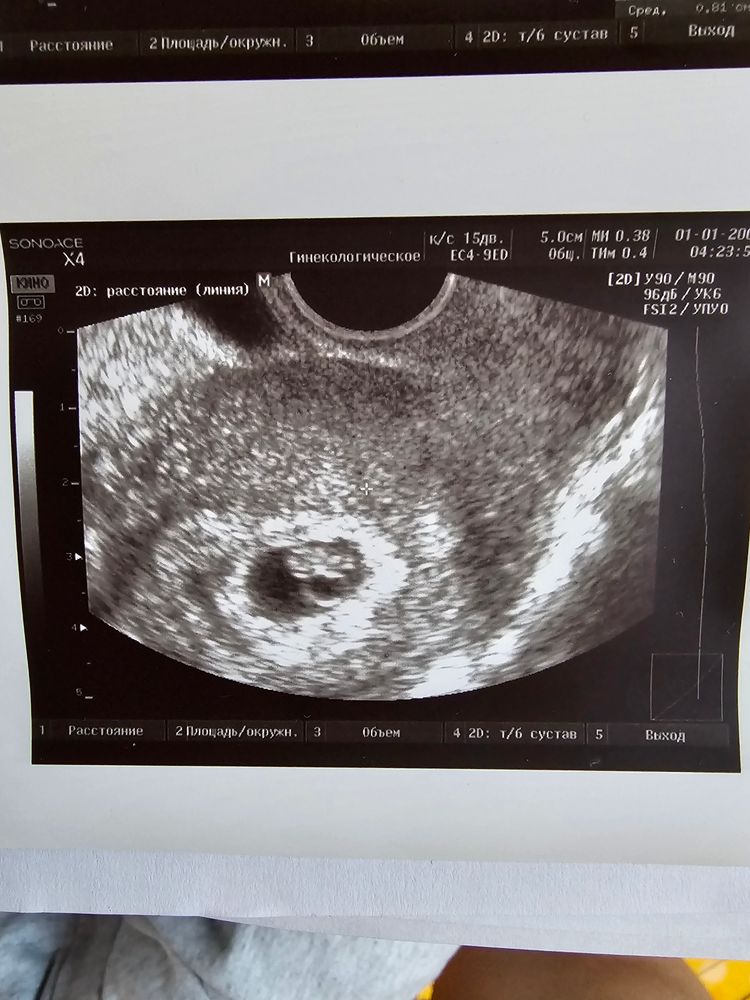

УЗИ-подтверждение после ЭКО

Поздравляю! 🎉 Это на какой дпп узи ?

Екатерина, спасибо 🫶 Это 30 ДПП